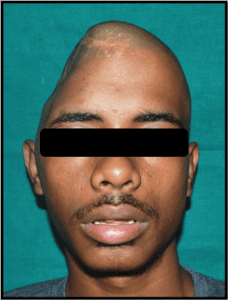

The Department of Prosthodontics and Crown & Bridge, in association with various Departments of Goa Medical College (Neurosurgery, Plastic Surgery, Surgery, Ophthalmology, and ENT), carries out complex rehabilitations of patients suffering from various developmental and acquired defects.

- Prostheses for maxillofacial defects